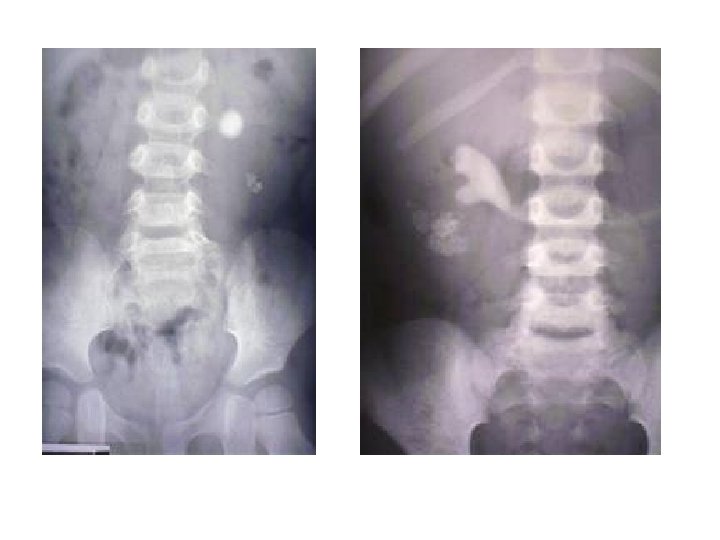

Radyolojik İnceleme • • • Direkt Üriner Sistem Grafisi Ultrasonografi İntravenöz Piyelografi Bilgisayarlı Tomografi Böbrek Sintigrafisi